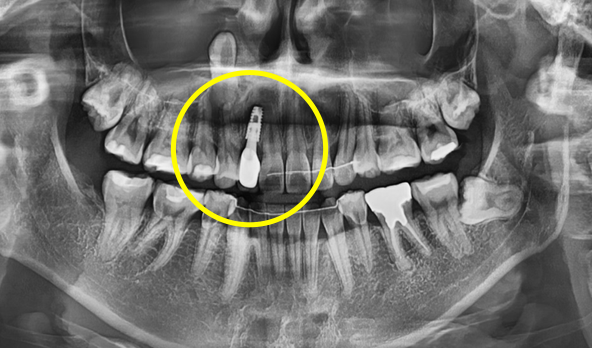

발치 후 수술용 가이드를 이용해 정해진 위치에 정확하게 식립 후 미리 만들어 둔 기둥 연결

발치 후 수술용 가이드를 이용해

정해진 위치에 정확하게 식립 후

미리 만들어 둔 기둥 연결

수술 당일 보철물 즉시 완성

2개월 후 잇몸의 형태가 바뀌거나 필요 시 2차 보철물(최종보철물)로 교체

2개월 후 잇몸의 형태가 바뀌거나

필요 시 2차 보철물(최종보철물)로 교체

임플란트 최종 결과

BEFORE/AFTER

BEFORE

AFTER